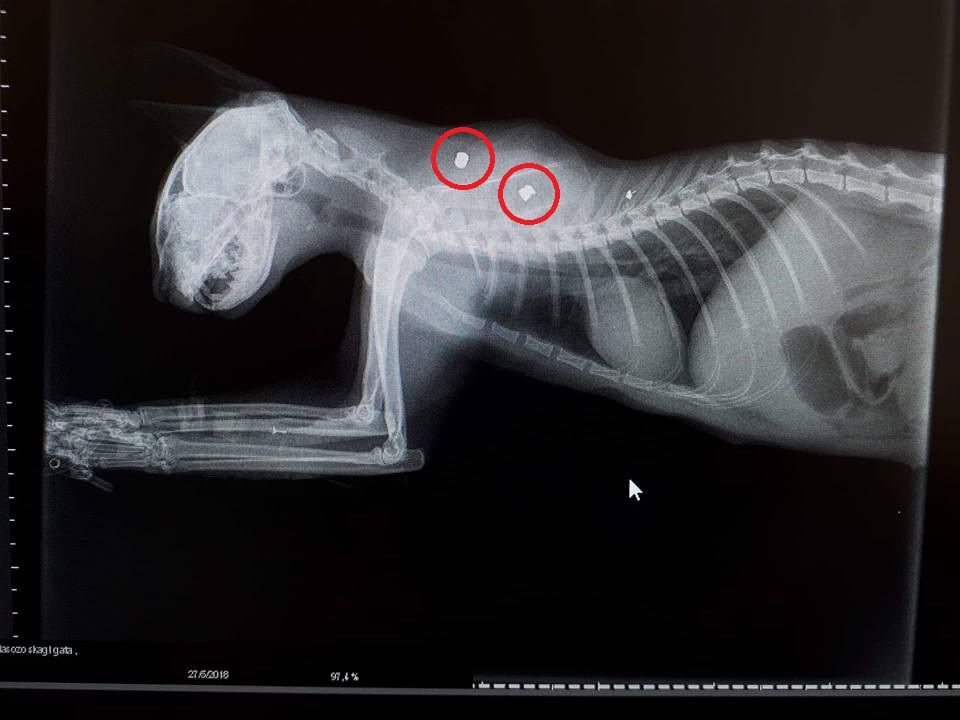

Σοβαρά τραυματισμένη στο μάτι εντοπίστηκε μια αδέσποτη γάτα στις 26 Μαΐου στην πόλη της Καρδίτσας και τελικά όπως έδειξε η ακτινογραφία το ζώο είχε πυροβοληθεί και μάλιστα δύο φορές με αεροβόλο όπλο.

Σύμφωνα με την Ερμιόνη Γιαννακού, που είναι αντιπρόεδρος του Φιλοζωικού και Πολιτιστικού Σωματείου Καρδίτσας «Διασώζω», το ζώο που βρέθηκε στην οδό Αμμόχωστου και μεταφέρθηκε στον κτηνίατρο, ο οποίος προχώρησε στη χειρουργική αφαίρεση του αριστερού οφθαλμού της γάτας που είχε καταστραφεί ολοκληρωτικά. Το ζώο «Νοσηλεύεται και ελπίζουμε να τα καταφέρει…» επισημαίνει η κα Γιαννακού η οποία κάνει και έκκληση για να καλυφθούν τα έξοδα νοσηλείας.